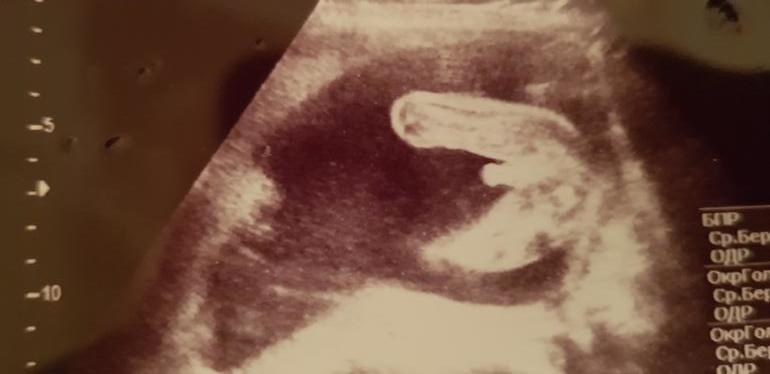

Пол малыша Привет, девочки! У нас неожиданно возникли сложности с определением пола малыша, в 20 недель сказали, что девочка, в 22 (было УЗИ по показаниям), что мальчик, в 29 сказали, что непонятно, то от девочка, то ли мальчик. Я запуталась 😳 Видимо, точно узнаем в сентябре только 😂 Но сейчас интересно порассуждать, как вы думаете, на кого больше похоже на девочку или мальчика? 😊

вот 100% мальчик))мне кажется у вас девочка))

Я больше к мальчику склоняюсь. На первом фото хорошо видно, на втором если увеличить и присмотреться, тоже что-то виднеется похожее на яички. Просто ракурс не очень. Вот у нас девочка, фото ровно 16 недель, не к чему придраться, и сейчас в 21 неделю ходили, между ножек ничего не выпячивается :)

Я бы по фото сказала, что мальчик. Но девочки правильно пишут - чаще получается, что если сомневаются на УЗИ или непонятно, девочки рождаются.